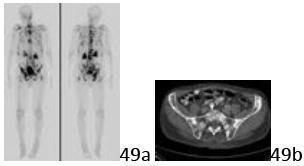

11. # 49a 49b An 85-year-old man reports diffuse pelvic and back pain that has progressed over the past 6 months. He also notes that he is chronically fatigued and is unable to get comfortable in any position. Figures 49a and 49b show a bone scan and a pelvic CT scan. On the basis of the history and the appearance of the studies, what is the most likely diagnosis??

DISCUSSION: The bone scan shows multiple areas of

bony activity, which would suggest metastatic disease or multiple myeloma in this age group. (Myeloma may not be hot on bone scan, but certainly can present on a bone scan in this fashion). The CT scan reveals multiple blastic lesions in the bone, which is typical of metastatic prostate cancer. Myeloma, renal carcinoma, and thyroid carcinoma would present with lytic lesions. Lung metastases are more commonly lytic lesions, presenting as blastic lesions approximately 25% to 30% of the time.

The Preferred Response to Question # 49 is 4.